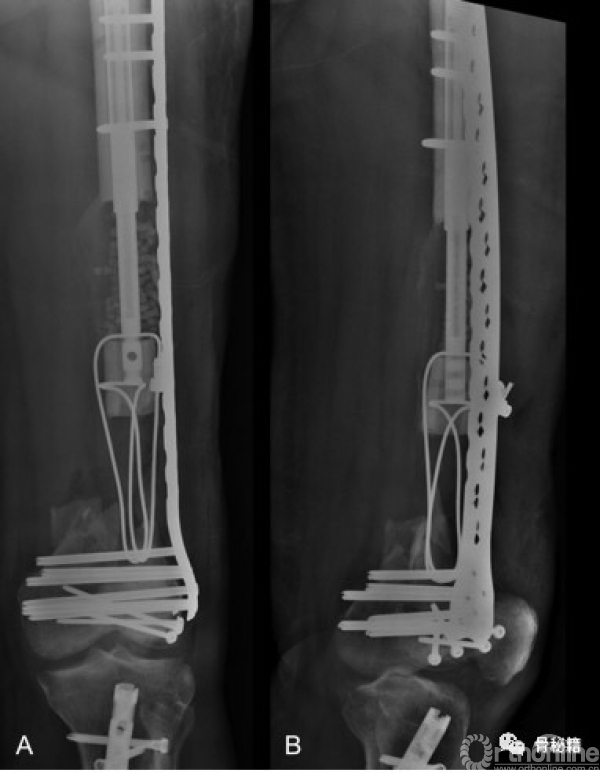

首先,感染控制住了,更换了内固定+磁力髓内钉+一组滑轮

由于远端大量骨缺损,先行了Liss钢板固定远端

同时给与近端股骨磁力髓内钉,同时进行截骨

滑轮是将截骨近端和远端锁定进行了一个套索,但是远端选择了游离

按照此路径进行了骨延长后,可见骨的生长,截骨块已经延长了一部分

此时去掉了髓内钉远端的锁定,将髓内钉稍微短缩了一些,露出远端的锁定孔

将捆绑线穿过髓内钉的远端锁钉控,继续延长到了髓内钉的极限位置

将滑轮组翻转,一端再髓内捆绑到髓内钉的远端,另外一段经过远端锁定孔后固定于骨折块,然后进行髓内钉的短缩,就通过滑轮原理继续进行了骨折块的搬移